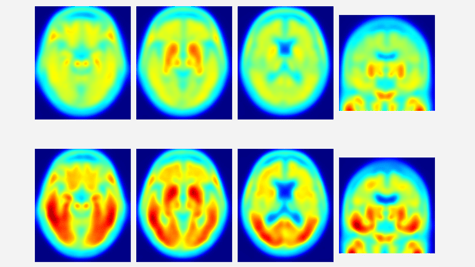

Les progrès rapides et considérables de l'imagerie (en particulier fonctionnelle), permettent de diagnostiquer les lésions cérébrales -dont la maladie d'Alzheimer- à des stades de plus en plus précoces.

La tomographie par émission de positons (TEP ou Pet-Scan) est particulièrement adaptée et performante pour cet usage.